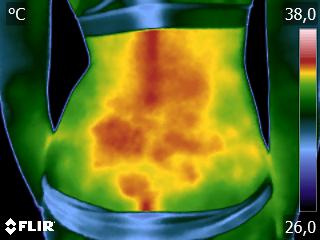

Como no caso do termograma abaixo de um paciente do sexo masculino, 52 anos, sem comorbidades e que apresenta dor em ombro após treino de musculação. Foi realizado uma Análise Termofuncional e detectado alterações térmicas condizentes com o relato de dor.

Segundo os conhecimentos da Termofuncional, estes resultados representam sobrecarga tecidual, podendo estar ligada a biomecânica errada. Através destes conhecimentos é possível o terapeuta partir para uma análise focada na biomecânica e na carga de treinamento, corrigindo ambas.

Além, claro, de permitir um mapa para escolhas de tratamento através de métodos e técnicas terapêuticas que o profissional achar adequado. Ao longo da reabilitação, também é possível o profissional monitorar os resultados alcançados para aumento da eficácia do tratamento.

Tudo isso também permite o registro documental que é a sua segurança e a do paciente. Nenhuma outra técnica permite, de forma autônoma, um registro documental tão preciso como este.